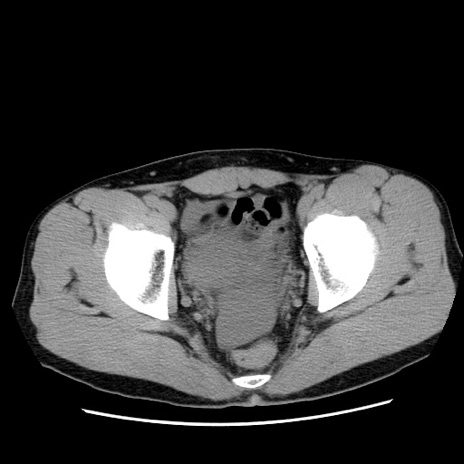

冠状断像